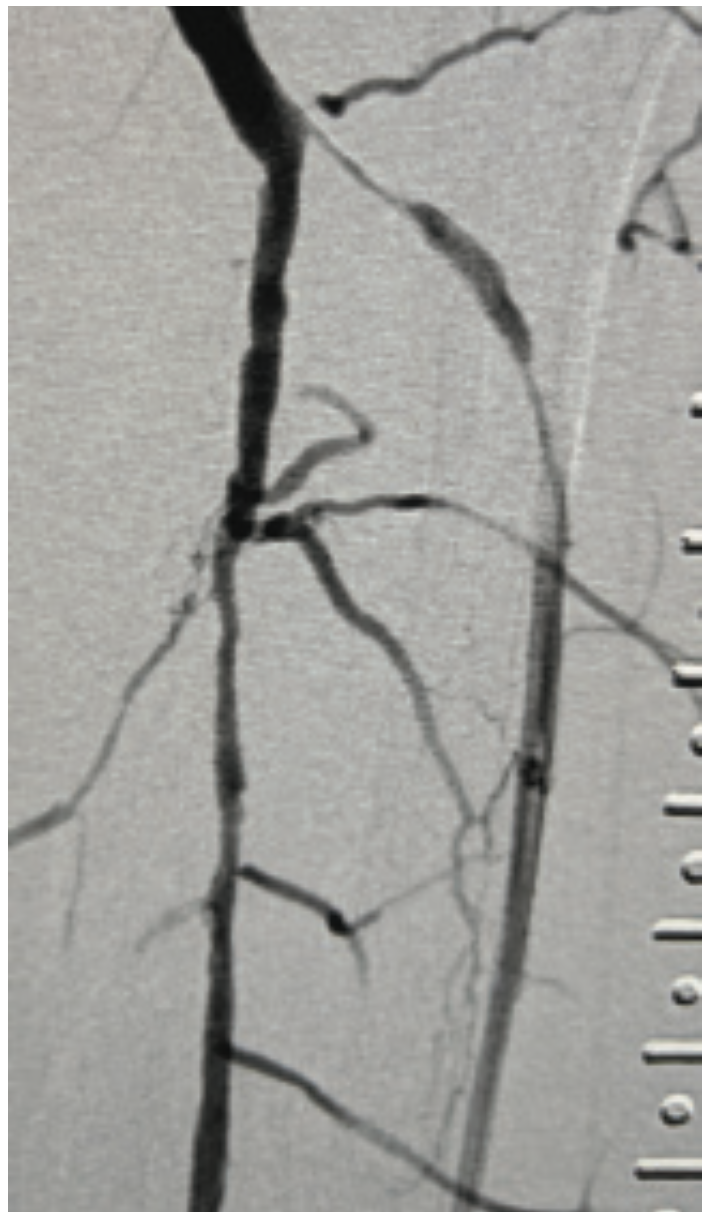

This is a 71-year-old male with a prior history of aortic valve replacement on coumadin, peripheral arterial disease, myocardial infarction, diabetes, and chronic kidney disease. He presented with a 3-month history of ischemic rest pain involving the left lower extremity, no wounds. He had previously undergone left superficial femoral artery (SFA) stenting for a chronic occlusion, but despite this, continued to have rest pain with peroneal-only runoff (Figures 1-4). He was brought in for left anterior tibial artery recanalization.

The patient qualified for the MicroMedical MicroStent trial, and both antegrade left lower extremity and retrograde dorsalis pedis access were obtained. The TASC II type D lesion of the anterior tibial artery origin was crossed with a V-18 wire (Boston Scientific), from below, and the wire was externalized via the antegrade sheath. Additionally, an .014-inch wire and balloon were placed into the tibioperoneal trunk and a 3 mm balloon was inflated across the origin of the anterior tibial artery. This “SOBE balloon protection technique” was used both to mark the origin of the anterior artery as well as serve as a buttress for placement of the stent (Figure 5). A 3 mm x 40 mm MicroStent was chosen and advanced through the 3 French (Fr) sheath from the dorsalis pedis access to the anterior tibial artery origin. The stent was placed across the lesion with precision to the origin. A 3 mm balloon was then inserted through the portal access and the stent was dilated to profile. Then the tibioperoneal trunk balloon was deflated and completion angiography was performed. Inline flow had now been created to the foot via the peroneal and anterior tibial arteries (Figure 6).

This is a technique we developed (SOBE stands for “South Beach”). We had a patient that needed to have the stent dropped on a dime on the proximal aspect of the anterior tibial artery. A balloon was placed down from above into the tibioperoneal trunk, then inflated in the tibioperoneal trunk, where there was a lesion as well. We came from below and were able to use the balloon as a buttress to advance the stent all the way up to where the balloon was, at the ostium of the anterior tibial. There we deployed the stent and released it from the retrograde tibial approach, placing it over about a 4 cm length and then post dilating the stent. This technique allowed for perfect placement at the ostium of the anterior tibial using the balloon as a guide or buttress.

This patient had significant tibial disease involving the ostia of the vessels. He didn’t have wounds, but he did have rest pain. There are two reasons this patient was a good candidate for the MicroStent and the SOBE balloon protection technique: the tibioperoneal trunk was open so there was a way to cross the origin of the AT, and size-wise, it was a 3 mm vessel (and the bigger, the better, with the tibials). As Dr. Jihad Mustapha has reported, tibial sizing is important, whether confirmed angiographically or by intravascular ultrasound (IVUS). The anatomy was good; there was a short lesion at the anterior tibial origin and we were able to cross that area to put up the balloon in order to protect the origin. The stent had a perfect landing. In general, when I place tibial stents, it is nice to have a focal, shorter lesion, because patency tends to be better in that situation.